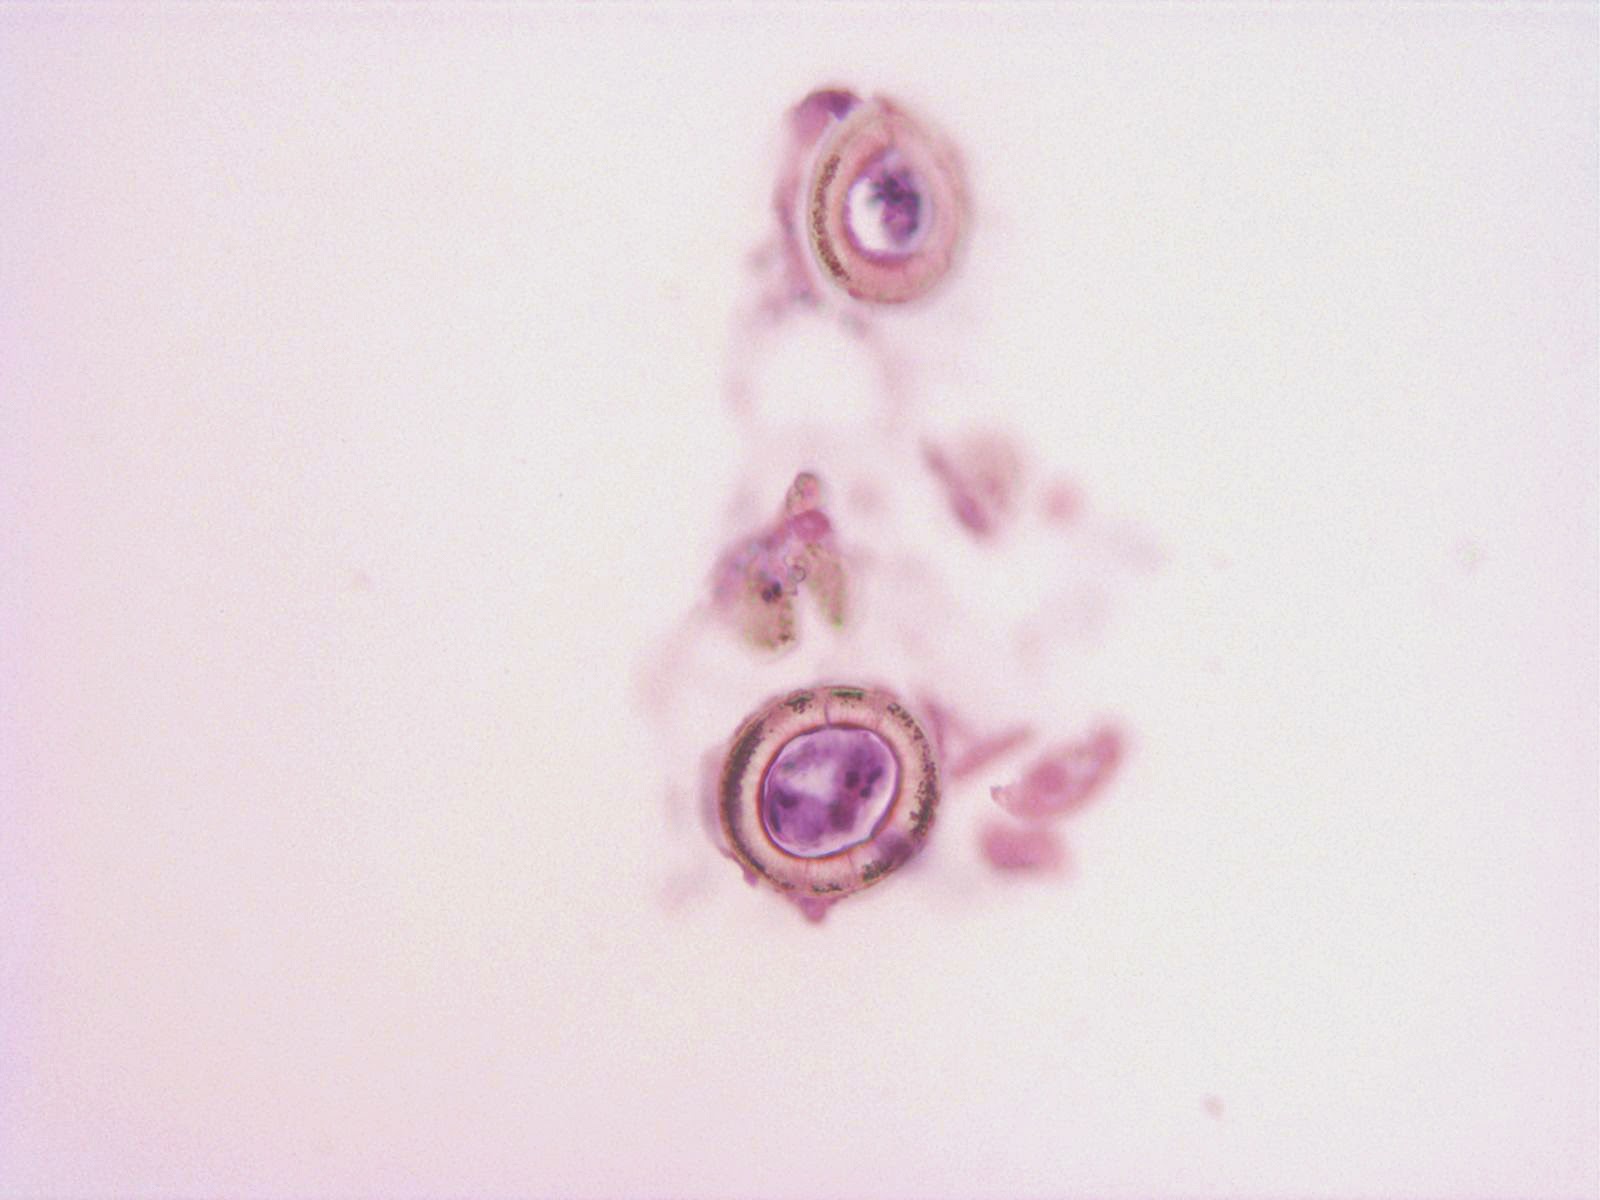

Happy New Year to all of my Readers! Here is a special case for the start of 2015 - the beginnings of a parasite. These eggs were found in stool and measure approximately 60 micrometers in greatest dimension.

Would you normally expect to find this stage of egg in a human stool specimen?

Answer: Ascaris lumbricoides ova, fertile

What makes this case somewhat unique is that there is a larva inside of each egg. As noted by Anon and Dr. Leisure, you would not expect to see an embryonated egg in a fresh stool specimen. Instead, eggs are passed from the human host in the unembryonated form and then develop in the soil into the infectious embryonated form containing a larva. However, if you have eggs in archived stool specimens - even in specimens preserved in formalin - the eggs can continue to develop as they would in the soil. That is what happened in this case. These eggs were seen in a stool specimen that had preserved in 10% formalin for several months, and larvae could be seen moving inside of the eggs! This is why I always teach my students that formalin will not reliably kill all parasites and that it is important to treat all specimens as if they are potentially infectious.